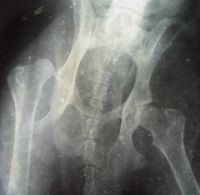

Клинический пример дисплазии ТБС у метиса овчарки. Снимок сделан 28.12. 2003

thumb 016Размечены углы на рентгеновском снимке.Тангенциальный угол положительный, Норнберга 90 гр.ре- ШДУ 135 гр. Угол ретроверсии 11гр. (при норме 15-17 гр.) Экзостозы на переходе головки в шейку бедра